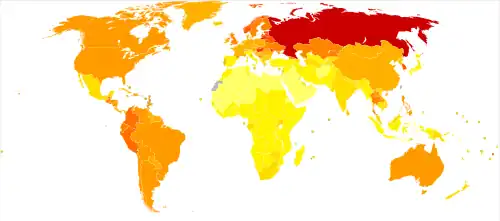

The world

The available evidence is in agreement that current drinking levels are too high. The WHO has emphasized the need to revise alcohol control policies worldwide in order to reduce overall alcohol consumption.[2]

Globally, assuming the J-shaped curve is correct, the age-standardised, both-sexes consumption that minimizes risk is about 5 grams of ethanol per day, and an average individual would cause themselves harm by drinking more than 17 grams per day.[11] However, the average intake among current drinkers in 2016 was approximately 40 grams of ethanol per day.[a] 1.03 billion males (35.1% of the male population aged ≥15 years, ~2/3 of male drinkers) and 312 million females (10.5% of the female population aged ≥15 years, ~1/3 of female drinkers) consumed harmful amounts of alcohol.[11][b] The proportion of the population consuming harmful amounts of alcohol has stayed at approximately the same level over the past three decades.[11]

Estimates of the worldwide number of deaths per year caused by alcohol vary. The 2016 Global Burden of Disease (GBD) study estimated 2.8 million, while the 2020 GBD study estimated 1.78 million.[47] The WHO estimates 3 million deaths per year from harmful use of alcohol, representing 5.3% of all deaths across the globe.[48] All of these numbers are net deaths, subtracting deaths prevented from deaths caused. Professor Tim Stockwell, former director of the Canadian Institute for Substance Use Research argues that alcohol may not prevent any deaths and guesses that as many as 6 million deaths may be caused by alcohol.[47] Besides this, the WHO attributes 5.1% of the global burden of disease and injury to alcohol, as measured in disability-adjusted life years (DALYs).[48] The WHO does not list alcohol in its 2019 list of the top 20 leading causes of DALYs, but alcohol use disorder (AUD) would rank around #39, combining AUD with alcohol-related cirrhosis and liver cancer would rank between malaria (#19) and refractive errors (#20), and all alcohol-attributed DALYs would rank between stroke (#3) and lower respiratory infections (#4).[49] Similarly the number of alcohol-attributed deaths would rank between chronic obstructive pulmonary disease (#3) and lower respiratory infections (#4).[50]

Research of Western cultures has consistently shown increased survival associated with light to moderate alcohol consumption.[21][51][52] Australasia and Europe are also the locations with the highest levels of harmful alcohol consumption.[11] Researchers have investigated cultures with different alcohol consumption norms and found conflicting results.